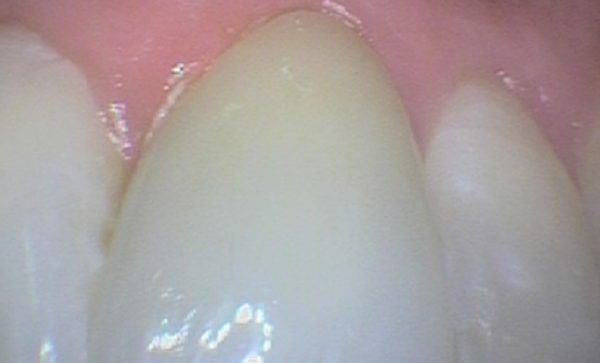

Case 21